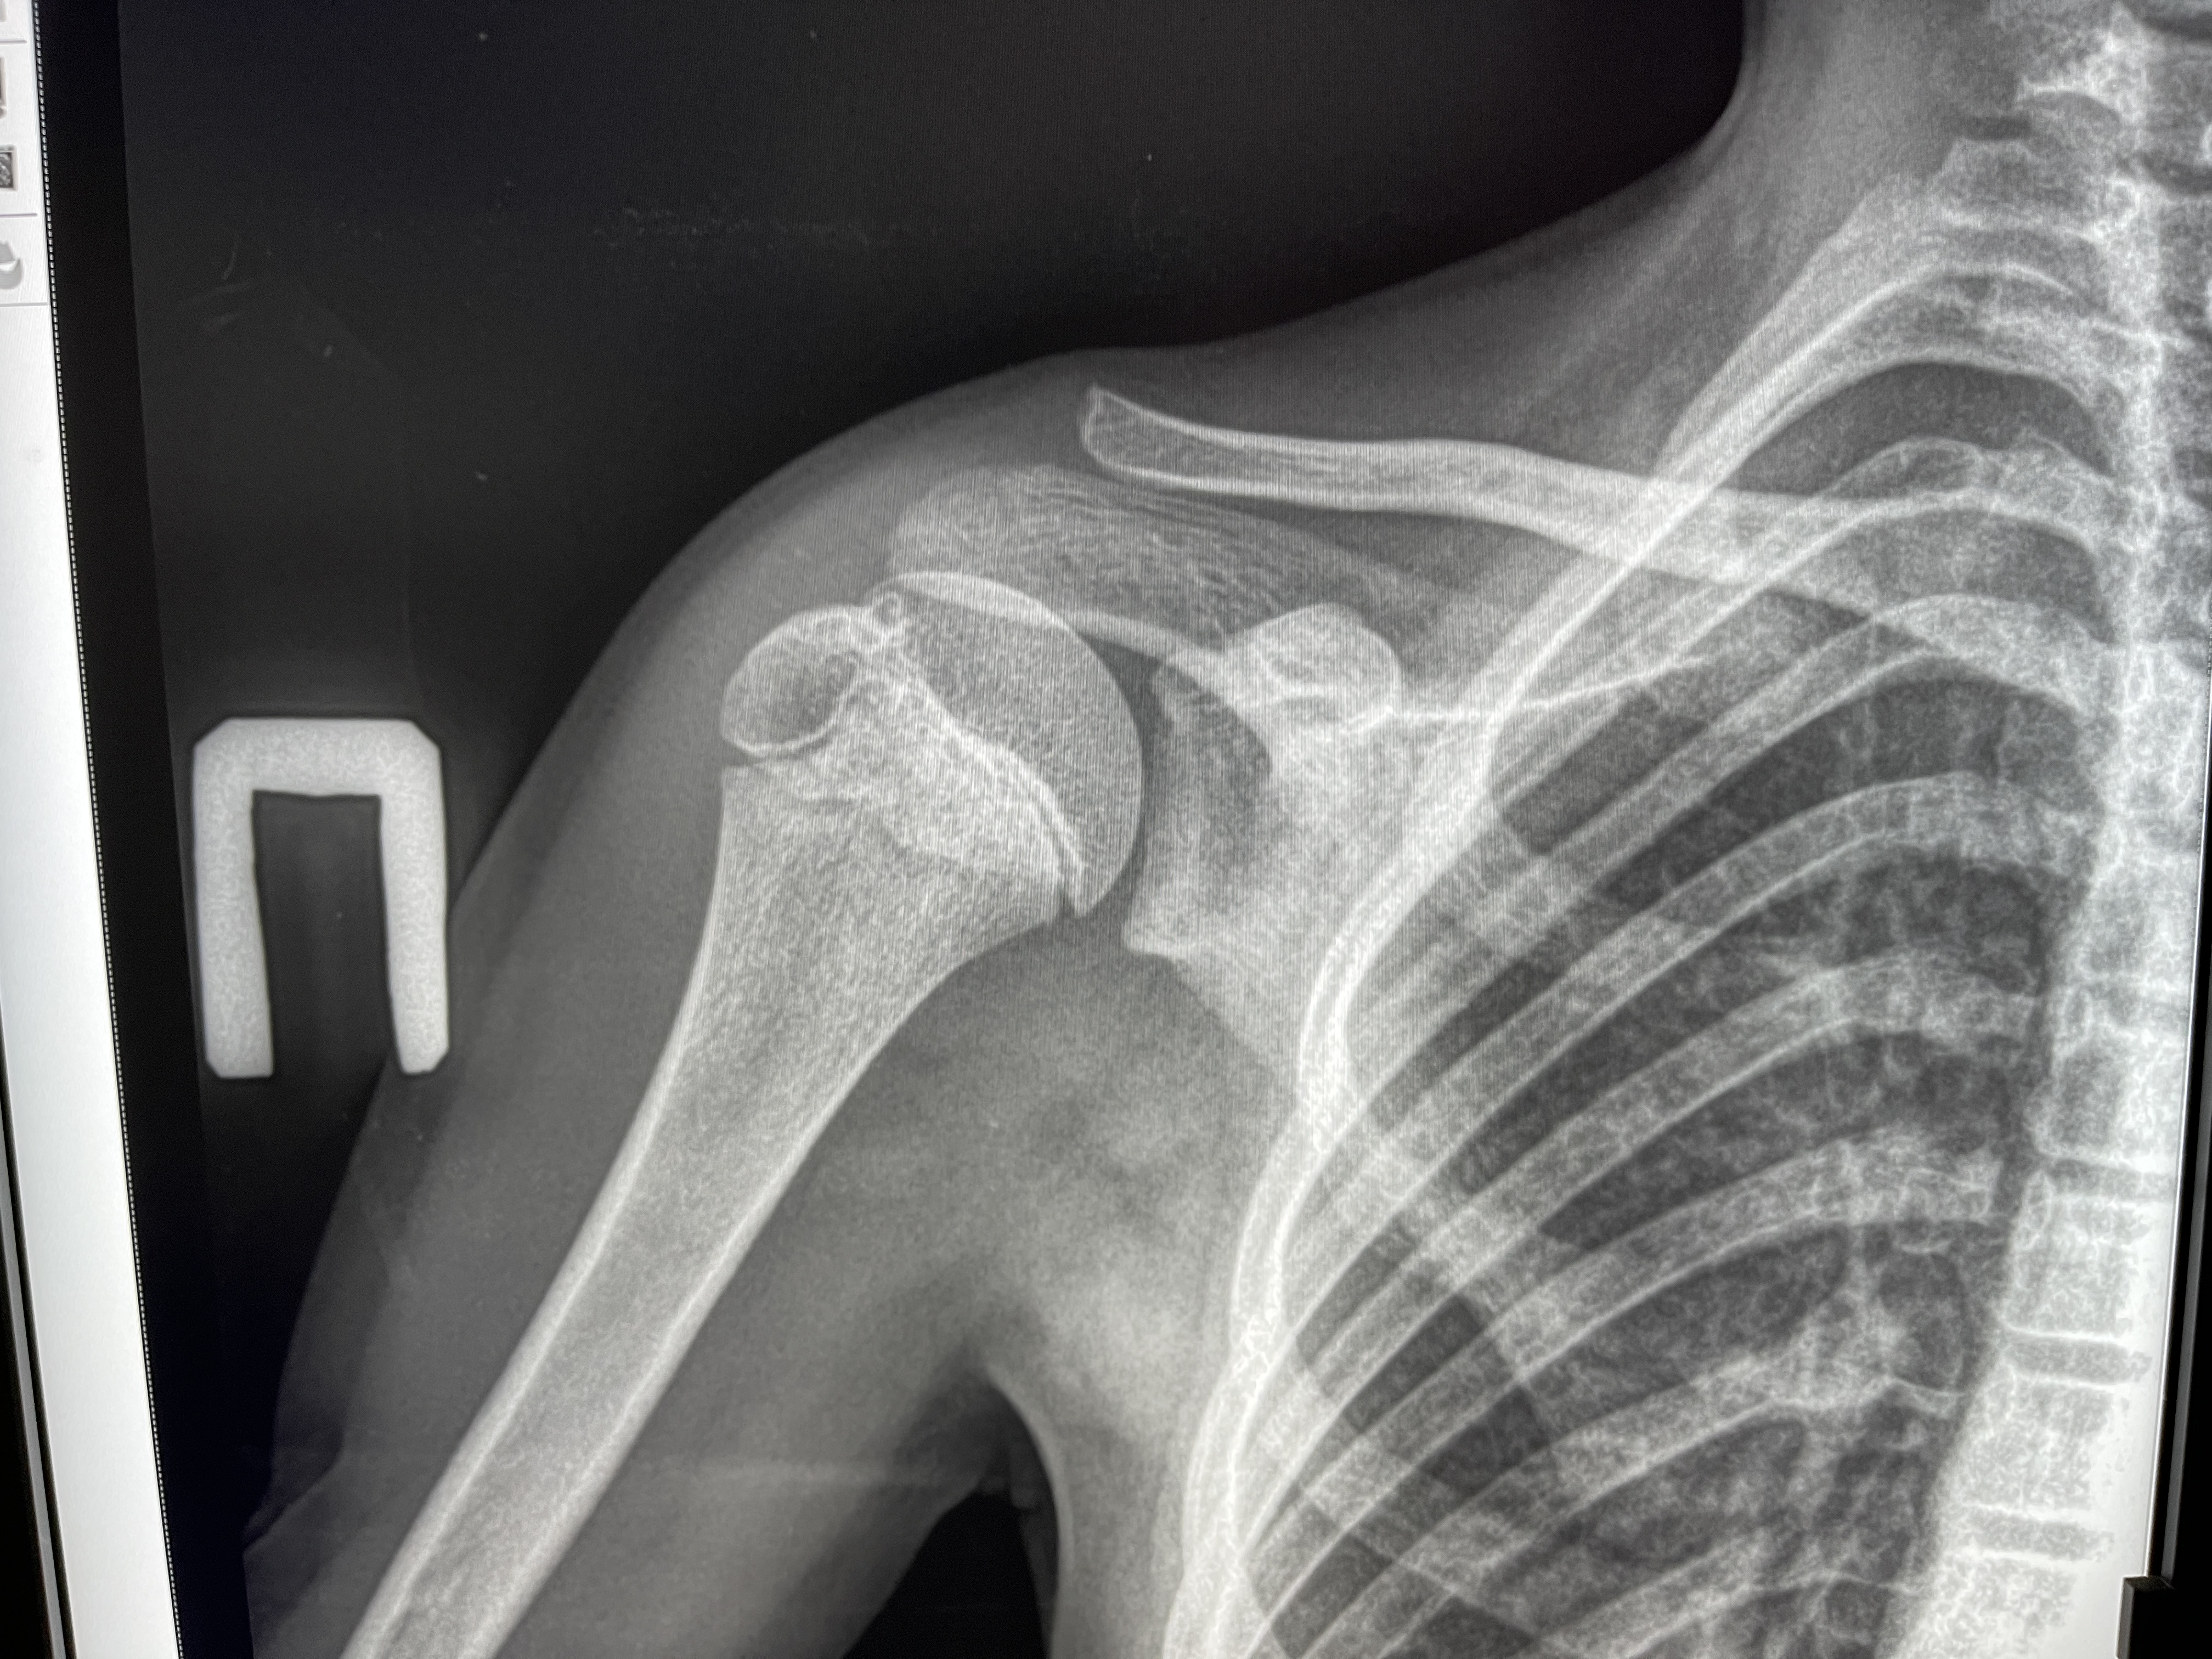

Нарост На Плечевой Кости Фото

Нарост На Плечевой Кости Фото 147 фотографий